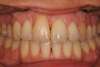

Rédicive d'un traitement dans l'enfance repris avec des gouttières

C-Début 3